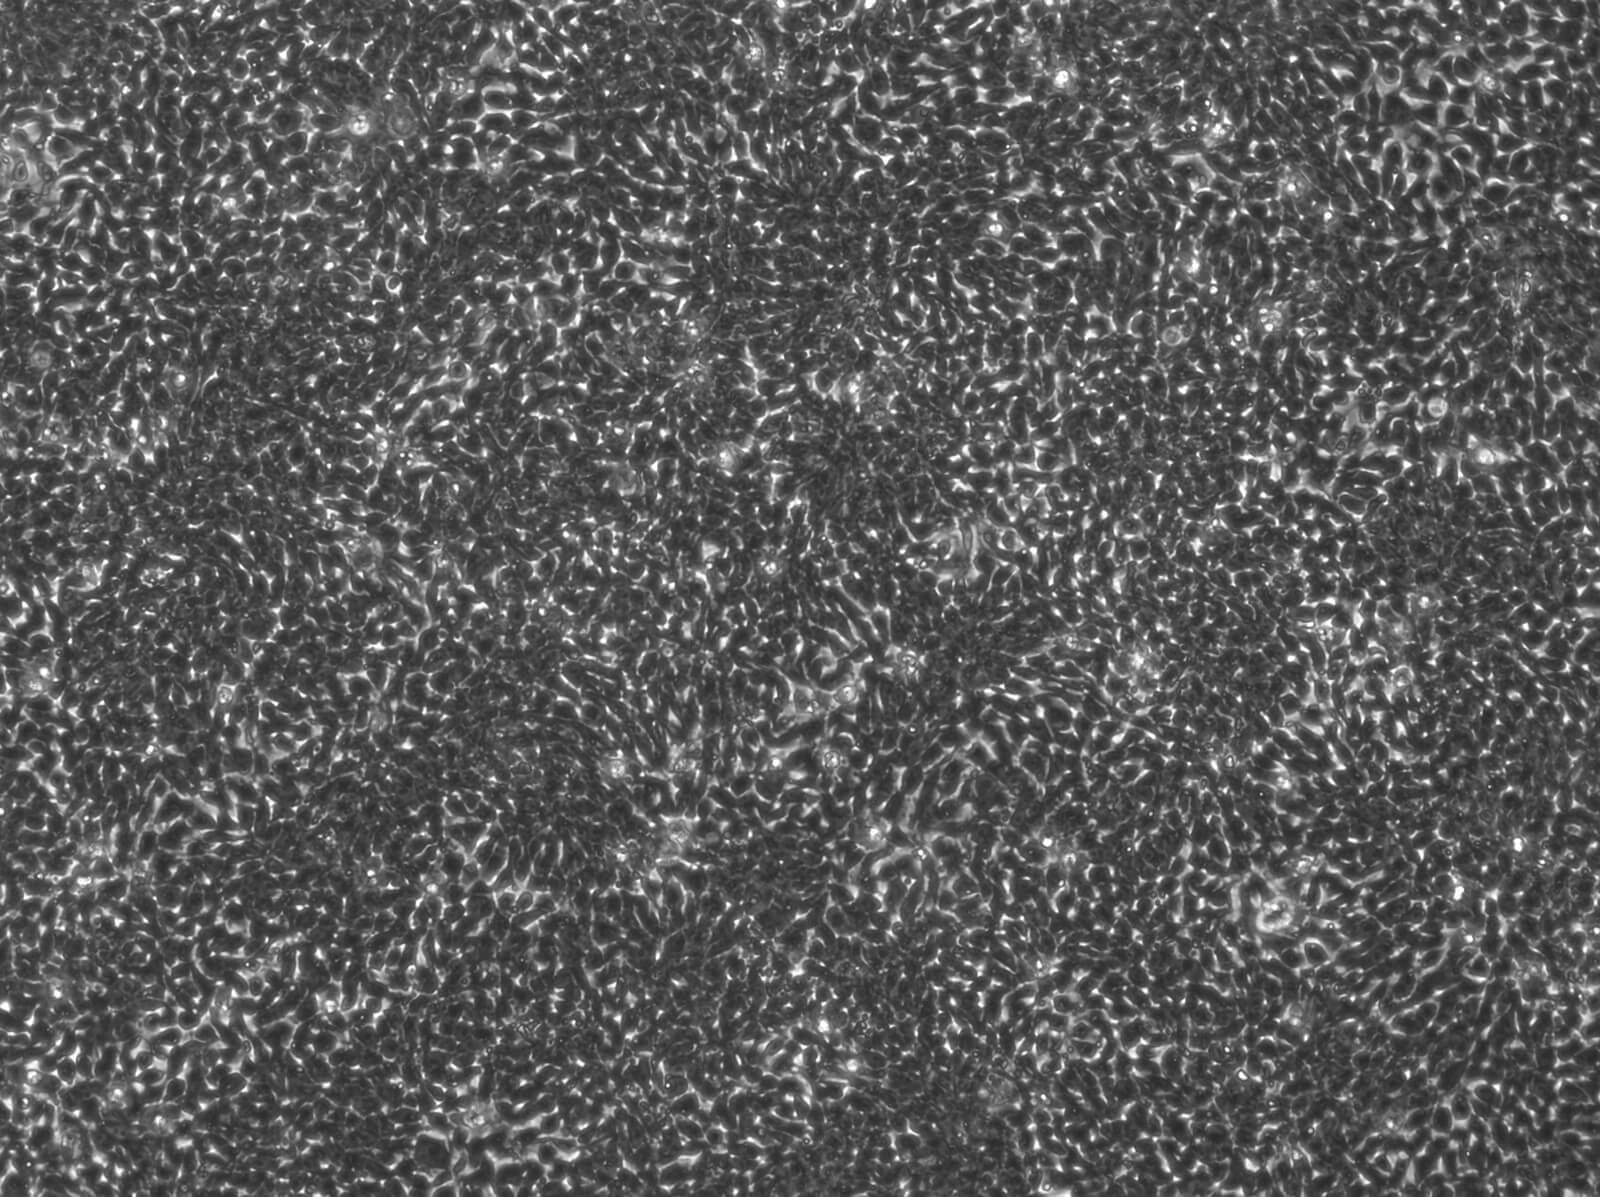

La sclerosi multipla (SM) è una malattia neurodegenerativa che colpisce il sistema nervoso centrale, causando infiammazione e danni ai neuroni. Nelle fasi avanzate, porta a una progressiva perdita di funzioni, dovuta all’azione del sistema immunitario, all’accumulo di lesioni e alla difficoltà del cervello di riparare il danno alla mielina, la guaina protettiva dei nervi. Oltre ai farmaci che regolano il sistema immunitario, c’è quindi un forte bisogno di trattamenti che proteggano i neuroni e rallentino la progressione della disabilità. Il progetto si propone di studiare il ruolo del recettore NK1R, una proteina coinvolta nei meccanismi di mielinizzazione e protezione del cervello. L’obiettivo è capire se possa diventare un nuovo bersaglio terapeutico per la sclerosi multipla. L’idea è quella di testare un farmaco già approvato per altri usi, con la speranza di accelerare lo sviluppo di una nuova terapia che favorisca sia la riparazione del danno che la protezione dei neuroni.